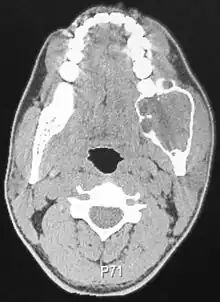

| Ameloblastoma of the mandible | |

Radiographically, the tumour area appears as a rounded and well-defined lucency in the bone with varying size and features. Numerous cyst-like radiolucent areas can be seen in larger tumours (multi-locular) giving a characteristic "soap bubble" appearance. A single radiolucent area can be seen in smaller tumours (unilocular).[8] The radiodensity of an ameloblastoma is about 30 Hounsfield units, which is about the same as keratocystic odontogenic tumours. However, ameloblastomas show more bone expansion and seldom show high density areas.[14]

Lingual plate expansion is helpful in diagnosing ameloblastoma as cysts rarely do this. Resorption of roots of involved teeth can be seen in some cases, but is not unique to ameloblastoma.[10]